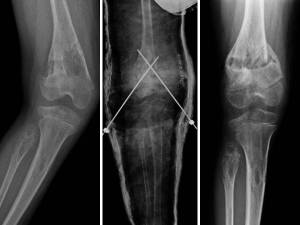

- Figg. 11 A-B-C: intervento di osteotomia

La correzione può essere attuata mediante intervento di osteotomia (fig 11), femorale o tibiale, a seconda della sede della deformità, oppure mediante interventi di modulazione della crescita, epifisiodesi asimmetrica temporanea, mediante applicazione di piccole placche a forma di “8” a cavaliere del versante interno della cartilagine coniugale del femore e/o della tibia (fig 12). Si tratta in questo caso di un intervento più semplice e meno aggressivo, che non richiede alcuna immobilizzazione in apparecchio gessato.

- Fig. 12A: ginocchia valghe in adolescente.

- Fig. 12C: aspetto RX dopo impianto delle placche sul versante mediale della cartilagine coniugale del femore e della tibia.

- Fig. 12B: placca a “8” e viti in titanio.

- Fig. 12D: Ginocchia in asse dopo pochi mesi.